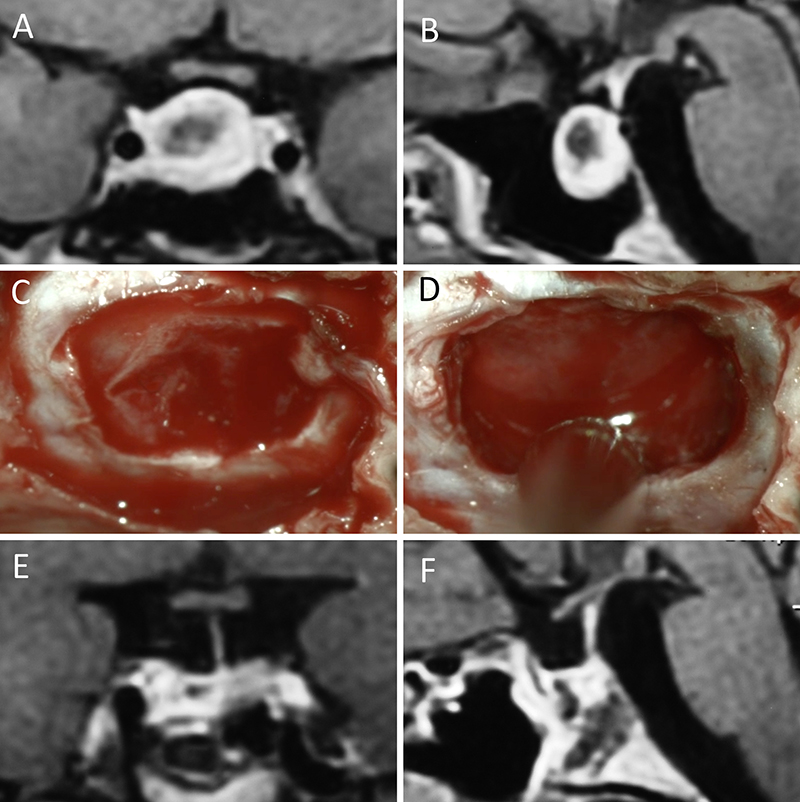

Figura 4: Macroadenoma no funcionante en mujer de 32 años. La paciente presentó en el preoperatorio déficit visual que mejoró tras la cirugía. A-B: RM preoperatoria; C-D: intraoperatorio; E-F: RM postoperatoria.